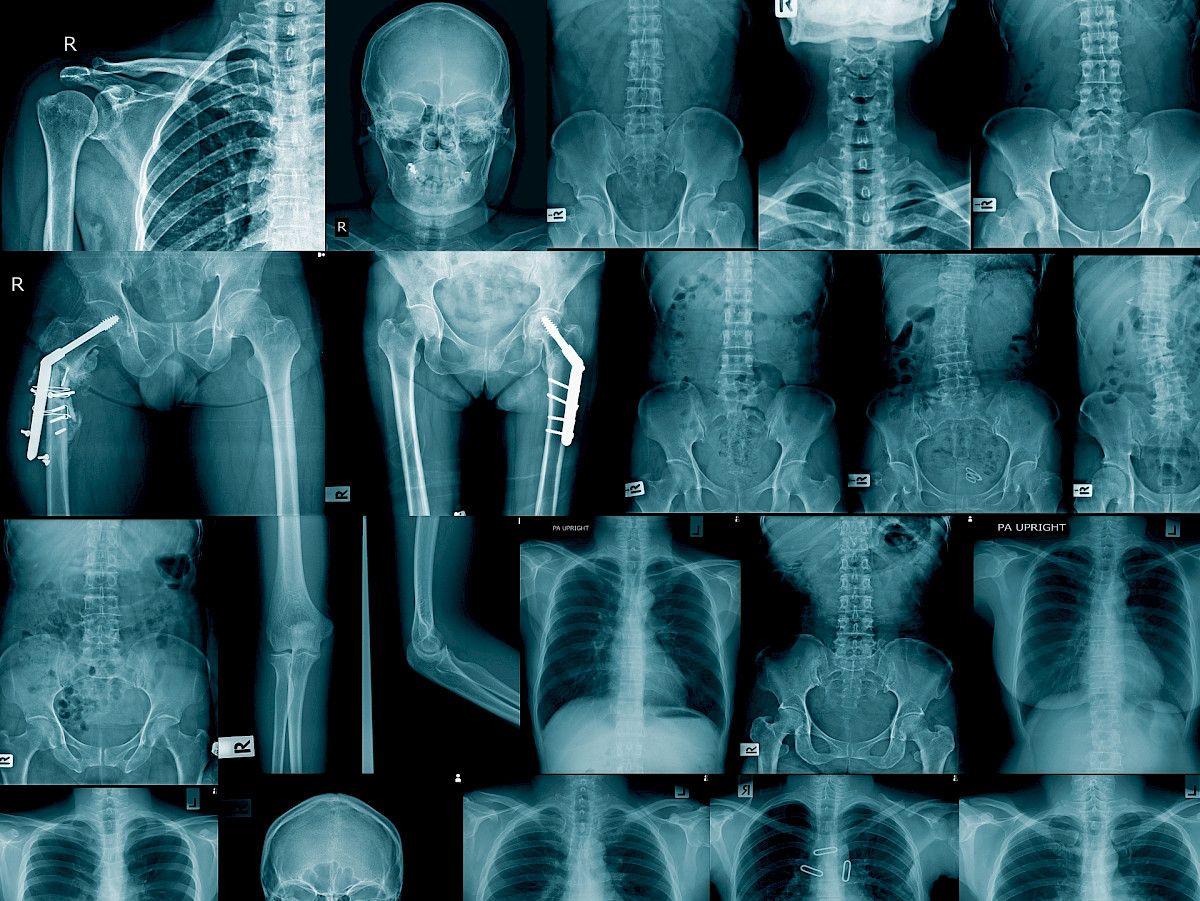

2. Uusi kategoria kuvantamiseen

Lakiin tulee uusi säteilyaltistuksen kategoria, joka korvaa oikeuslääketieteelliset tutkimukset. Se koskee henkilöön kohdistettua kuvantamista, jonka syy ei ole lääketieteellinen. Esimerkiksi hampaiston panoraamatutkimukset turvapaikanhakijoiden iän selvittämiseksi sekä huumeiden salakuljetuksesta epäillyn kehon kuvantaminen kuuluvat tähän kategoriaan, selventää Bly.